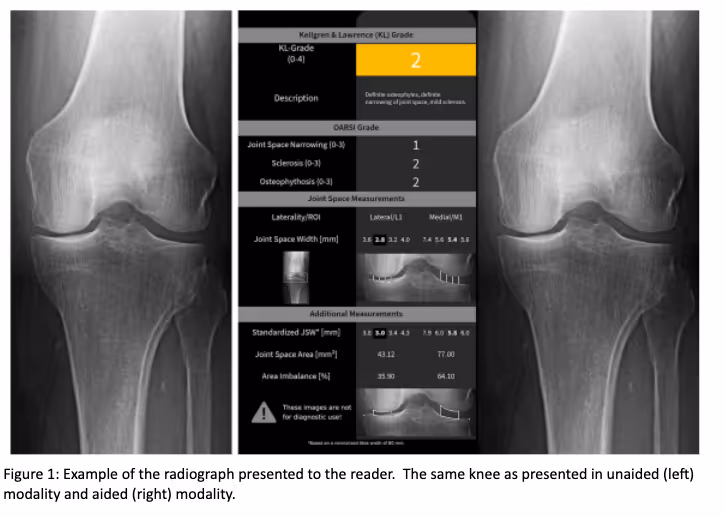

Ferrum Health partners with best-in-class AI providers offering solutions designed to reduce radiology workload and improve patient care.ImageBiopsy Case Study: AI Increases Physician Accuracy in Knee Osteoarthritis AssessmentOverviewVisual cues of early stages of osteoarthritis often elude radiographs which can lead to misdiagnosis, unnecessary examinations, and lack of treatment. Artificial intelligence (AI) has proven efficient in recognizing the complex visual patterns of osteoarthritis.InterventionIB Lab KOALA™(Knee Osteoarthritis Labeling Assistant), an AI system trained on a large dataset of radiographs has proven to statistically increase the accuracy rate of osteoarthritis diagnosis. KOALA analyzes anterior-posterior knee radiographs for the detection of features relevant to the diagnosis of osteoarthritis and provides readings for KL, JSN, sclerosis, and osteophyte OARSI grades.

In a study assessing diagnosis accuracy between unaided and AI-aided osteoarthritis diagnosis, KOALA reduced the false positive rate with little to no loss of true positive rate. Results show that the increase in accuracy of physicians is driven by an increase in specificity and sensitivity allowing physicians to better recognize the early stages of osteoarthritis.